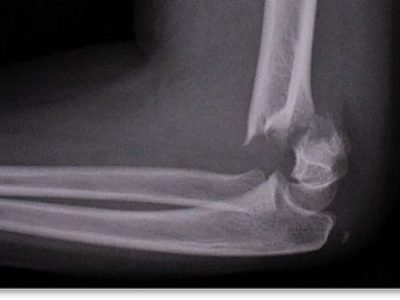

Tulang patah & Sendi dan otot

Sakit, ngilu & pedih bila bergerak